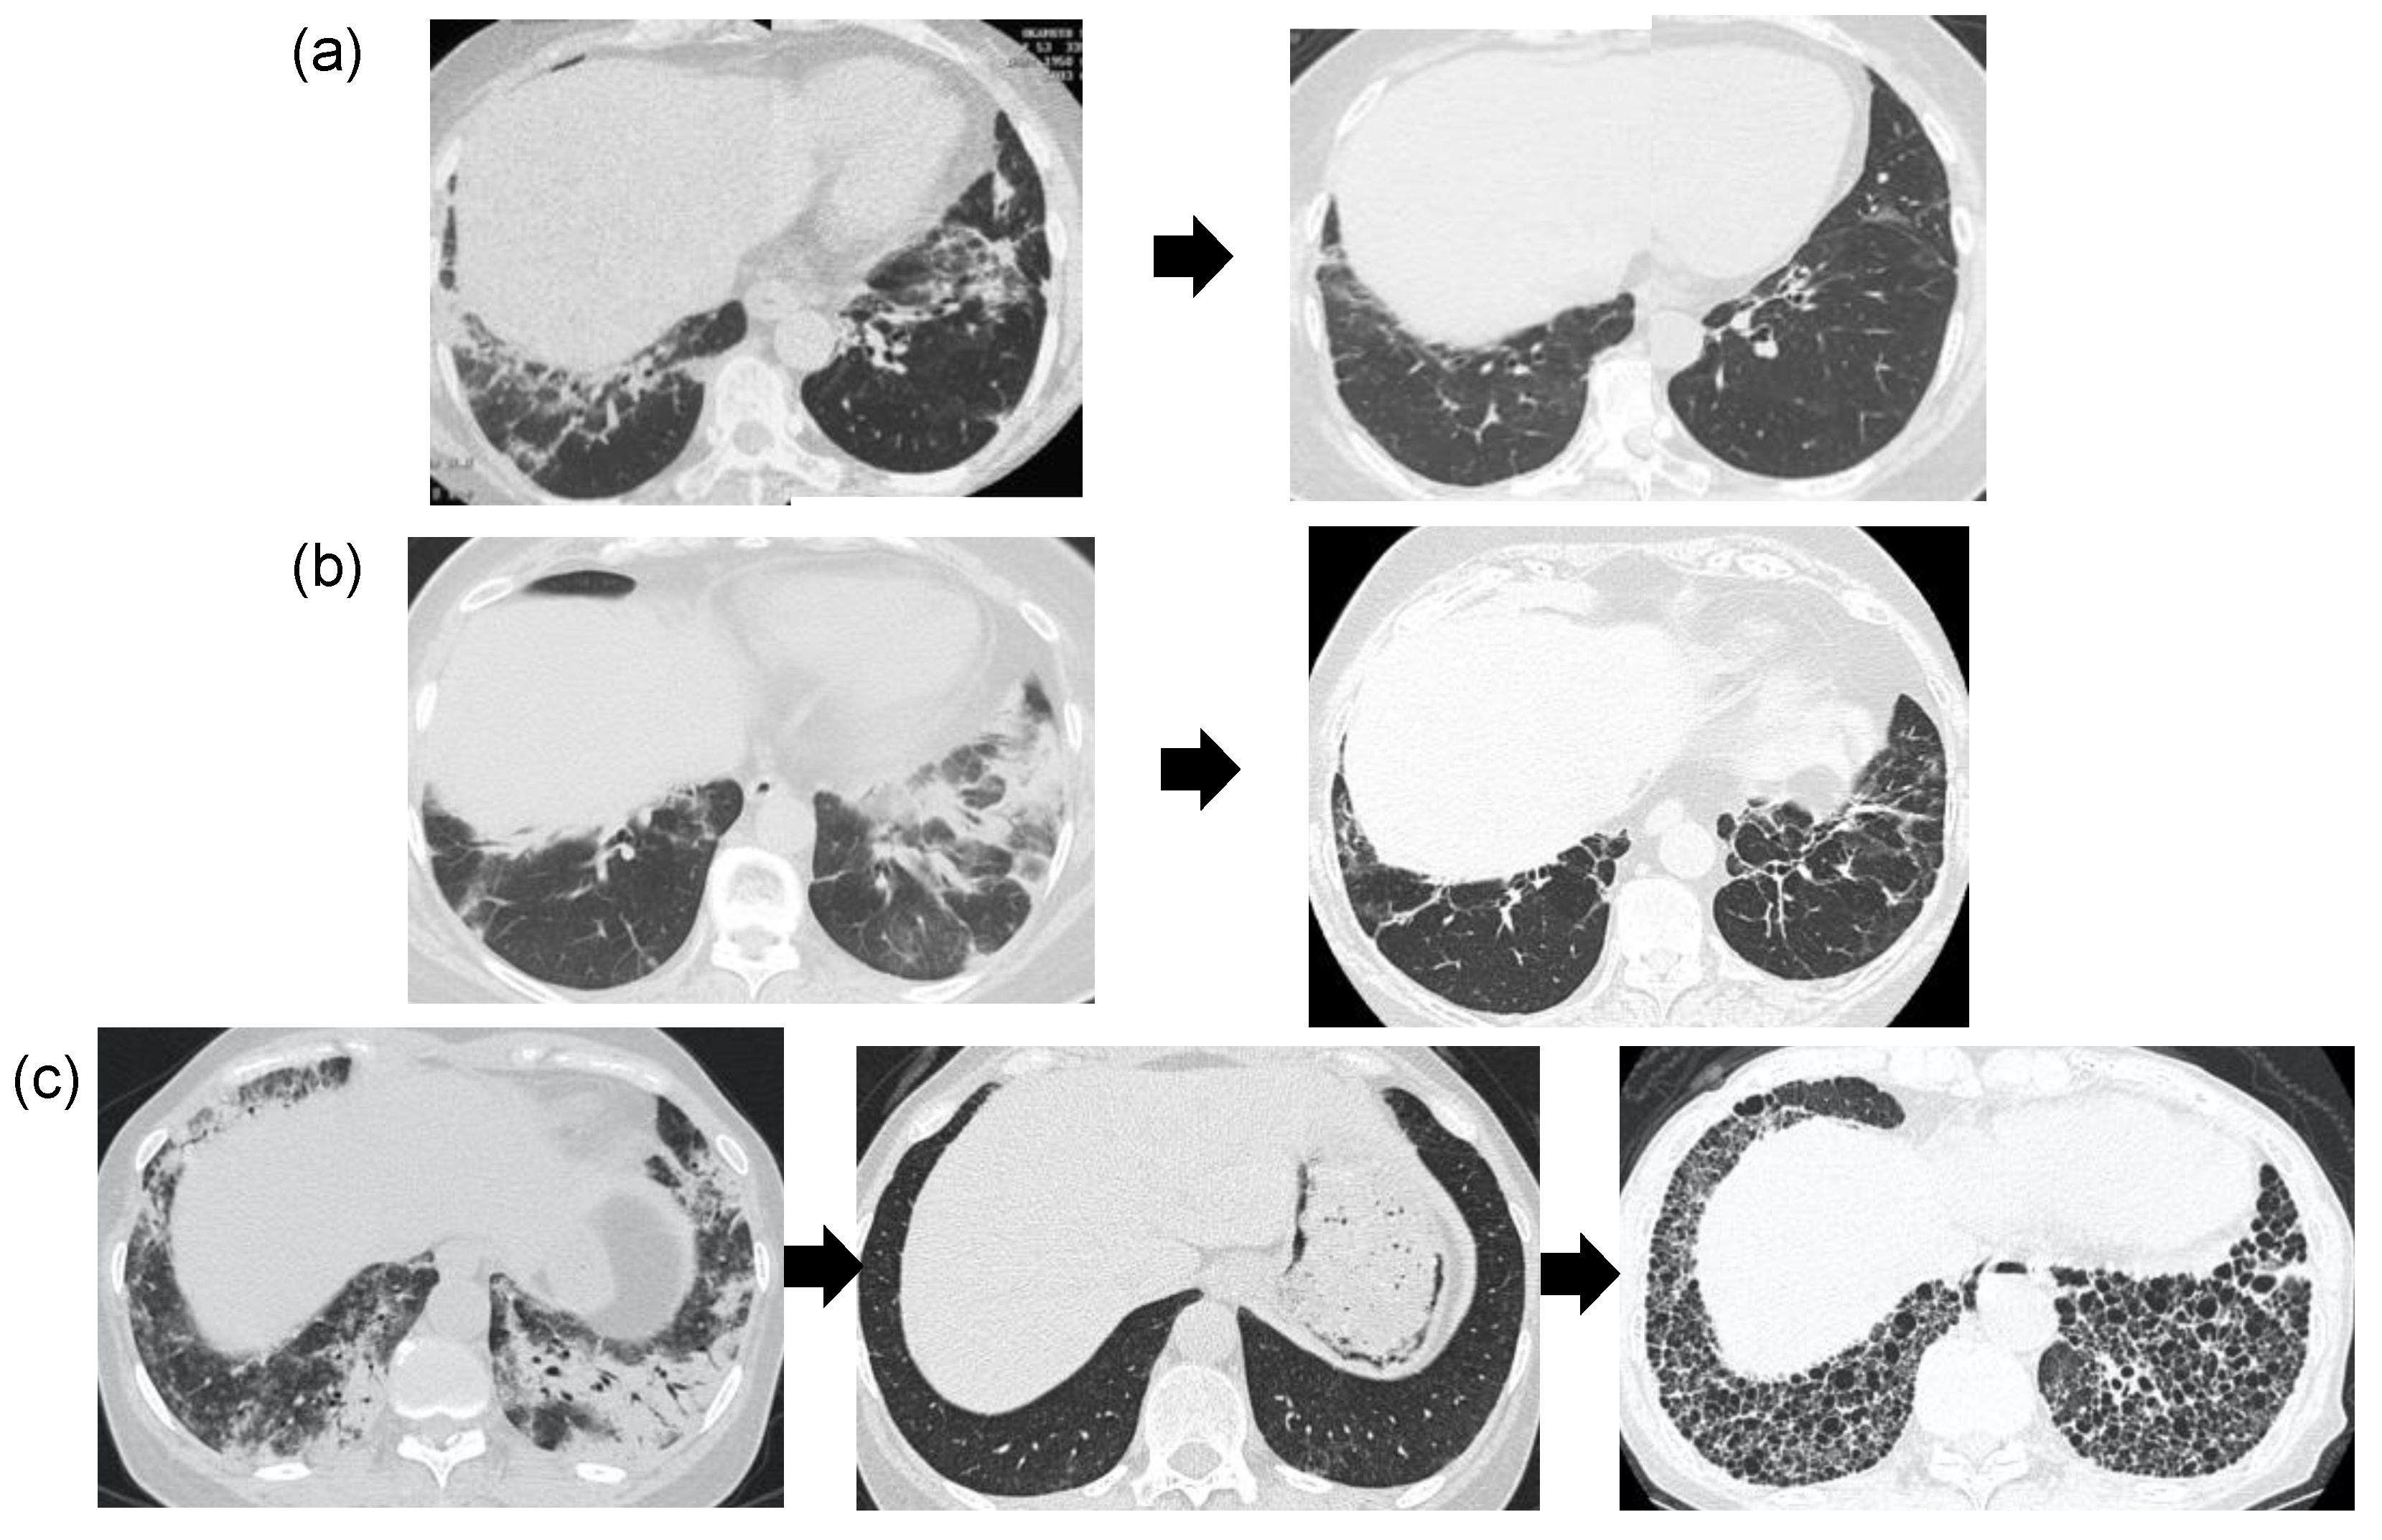

2.4. Imaging Test

- Waseda, Y.; Johkoh, T.; Egashira, R.; Sumikawa, H.; Saeki, K.; Watanabe, S.; Matsunuma, R.; Takato, H.; Ichikawa, Y.; Hamaguchi, Y.; et al. Antisynthetase syndrome: Pulmonary computed tomography findings of adult patients with antibodies to aminoacyl-tRNA synthetases. Eur. J. Radiol. 2016, 85, 1421–1426. [Google Scholar] [CrossRef] [PubMed]

- Waseda, Y.; Johkoh, T.; Prosch, H.; Nemec, S.; Saeki, K.; Watanabe, S.; Hamaguchi, Y.; Shiraki, A.; Muro, Y.; Yasui, M.; et al. Chest computed tomography findings of adult patients with antimelanoma differentiation-associated pro-tein 5 antibody-positive interstitial lung disease. Mod. Rheumatol. in press.

- Debray, M.-P.; Borie, R.; Revel, M.-P.; Naccache, J.-M.; Khalil, A.; Toper, C.; Israel-Biet, D.; Estellat, C.; Brillet, P.-Y. Interstitial lung disease in anti-synthetase syndrome: Initial and follow-up CT findings. Eur. J. Radiol. 2015, 84, 516–523. [Google Scholar] [CrossRef]